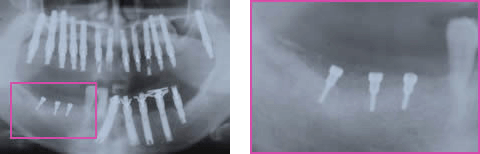

インプラント治療を希望し来院され、全顎的に高度の骨吸収を認めました(図1)。術前のCTデータをSimplantsにより3D構築し診断・計測したところ、下顎左側臼歯部の歯槽骨頂-下歯槽菅距離は第一第二大臼歯部で約9mmと近接、(図2)また、同部のハンスフィールド値からは歯槽頂部における皮質化の昂進を認めました(図3)。インプラント埋入には垂直的な骨高径獲得が必要不可欠であることから、vertical ridge augmentationを予定すると共に再生すべき垂直的骨量が約8mmであること、および同部の骨質から難易度の高さが予想されます(図4)。

初期治療終了後、下顎右側臼歯部に自家骨、Bio-oss、PRPおよびBio-Guideを用いてGBRを施行しました(図5)。しかし、予想はしていたものの移植骨は術後36週時には垂直的にその殆どが吸収されていました(図6)。そこで、目的の骨高径を得る為に超音波治療器による骨形成の促進を期待し再度GBRを施行しました。術式は前回と同様ですが吸収性メンブレンの下部にStraumanのmini screwを3本用いました(図7)。術後2週時より、1日1回15分を4週間、 超音波治療器を同部へ応用しました。設定は発振周波数3.0MHz、パルス幅2ms、パルス周期10ms、総出力:240mWとしました。

術後13週時のパノラマX線写真では予定した骨高径が得られており、移植骨と母床骨との境界は不明瞭でした(図8)。術後24週時のX線所見では予定した骨高径が得られており(図9)、翌週に同部にインプラントを4本埋入、造成した骨には豊富な血流が認められ、骨質は比較的硬く初期固定は十分に得られました(図10)。インプラント埋入後3ヶ月時にはオステオインテグレーションの獲得を確認し、現在プロビジョナルレストレーションにて機能負荷を開始しているが経過は良好です(図11)。

図5:下顎右側臼歯部 GBR

1回目GBR後1week

図6:1回目GBR後36week 移植骨の吸収

図7:下顎右側臼歯部 再GBR

1回目GBR後 12M 再GBR

図8:下顎右側臼歯部 再GBR後 13week

超音波治療応用後

中央部も境界不明瞭、近心部新生骨陵(+)